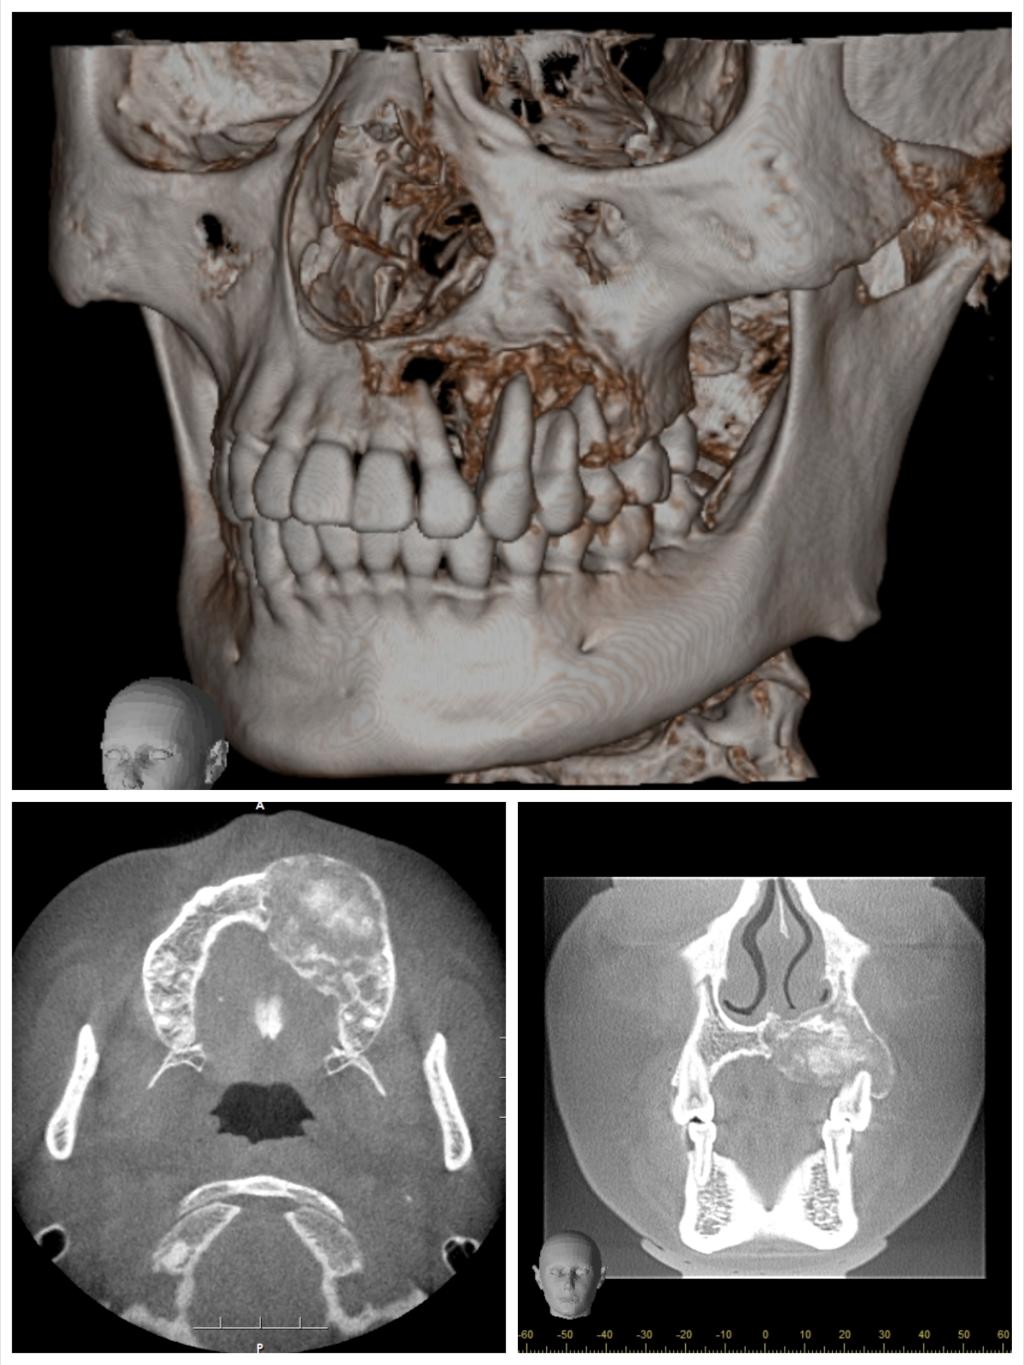

患者今年25岁,是一名年轻的母亲,1年前左侧上颌牙龈出现无痛性肿块,肿块逐渐增大,导致左侧面部畸形和牙松动。心急如焚的她咨询多家医院后,就诊口腔医院口腔颌面外科,口腔颌面外科主任吴亚东了解其病情后,制定了详细完善的个性化手术治疗方案,用血管化腓骨移植修复左侧上颌骨肿瘤切除后的缺损,既保证了术后不会因为硬组织缺失而导致面部塌陷,也能为后期种植牙修复提供足够的骨量。由于患者为年轻女性,为避免在面部留下明显的瘢痕,手术没有行上唇正中至鼻旁入路或下唇侧唇劈开入路,病灶切除及腓骨就位均在口腔内切口完成,但这也大大增加了手术难度。

目前,口腔医院完成血管化骨瓣移植修复重建下颌骨、血管化肌皮瓣修复软组织缺损已超百例,技术成熟,各类骨肌皮瓣存活率极高。但上颌骨肿瘤因临近鼻腔、上颌窦、眼眶等重要复杂结构,缺损的形态不规则,切除后缺损的修复有极大难度。上颌骨切除术后会导致口鼻瘘、面型畸形、语言及进食障碍、甚至对病人及其家属造成巨大的心理障碍。口腔颌面外科致力于解决患者的病痛,利用计算机辅助设计 / 计算机辅助制造(computer assisted design/computer assisted manufacture,CAD/ CAM),精准切除肿瘤及修复上颌骨缺损。术前设计、术中准确控制以及术后可靠预测,手术可获得理想上颌骨重建效果。在满足患者外形需求的同时,还保障了相关功能,真正做到了个性化功能性修复重建。